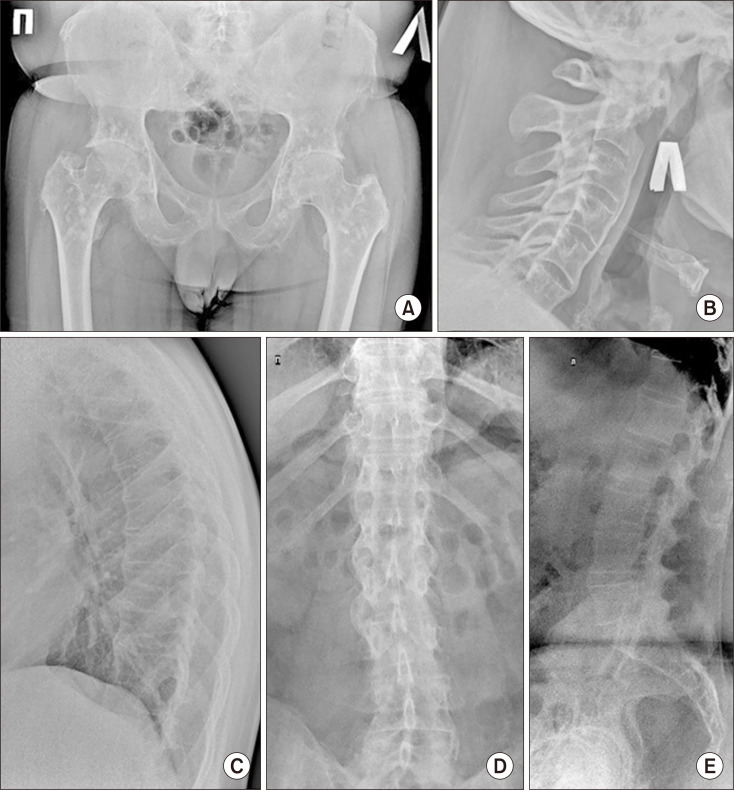

Osteopoikilosis (OPK) is a rare benign congenital genetic-mediated sclerosing skeletal disease, characterized by the formation of osteosclerosis foci. OPK is usually clinically asymptomatic, but some patients (15%~20%) may have arthralgia and synovitis. OPK may be associated with rheumatic diseases and might lead to unreasonable over-examination in real clinical practice. Single cases of the OPK together with ankylosing spondylitis (AS) have been described. Here we present a 33-year-old patient diagnosed with AS coexisting with OPK. In the case considered, the combination of AS and OPK accompanied with a high activity of inflammation, peripheral arthritis, a rapid rate of structural progression in axial skeleton, inefficiency of disease-modifying antirheumatic drugs and nonsteroidal anti-inflammatory drugs, a lack of response to anti interleukin-17 and a good response to a tumor necrosis factor inhibitor golimumab. We describe the important points of differential diagnosis associated with the identification of focal changes in bone tissue, especially neoplastic lesion. Foci revealed had typical localization, so, acquaintance of practicing doctors with such rare cases would minimize unnecessary examinations.

骨硬化症(Osteopoikilosis,OPK)是一种罕见的先天性遗传介导的良性硬化性骨骼疾病,以形成骨硬化灶为特征。OPK 通常无临床症状,但部分患者(15%~20%)可能会出现关节痛和滑膜炎。OPK 可能与风湿性疾病相关,在临床实践中可能会导致不合理的过度检查。已有单例 OPK 合并强直性脊柱炎(AS)的病例。在此,我们介绍了一名被诊断为强直性脊柱炎合并 OPK 的 33 岁患者。在该病例中,强直性脊柱炎和强直性脊柱炎合并症伴有高炎症活性、外周关节炎、轴向骨骼结构进展速度快、改善病情抗风湿药物和非甾体抗炎药物疗效不佳、对抗白介素-17缺乏反应以及对肿瘤坏死因子抑制剂戈利木单抗反应良好。我们描述了与识别骨组织病灶变化(尤其是肿瘤病变)相关的鉴别诊断要点。所发现的病灶具有典型的定位性,因此,执业医生对此类罕见病例的了解将最大限度地减少不必要的检查。